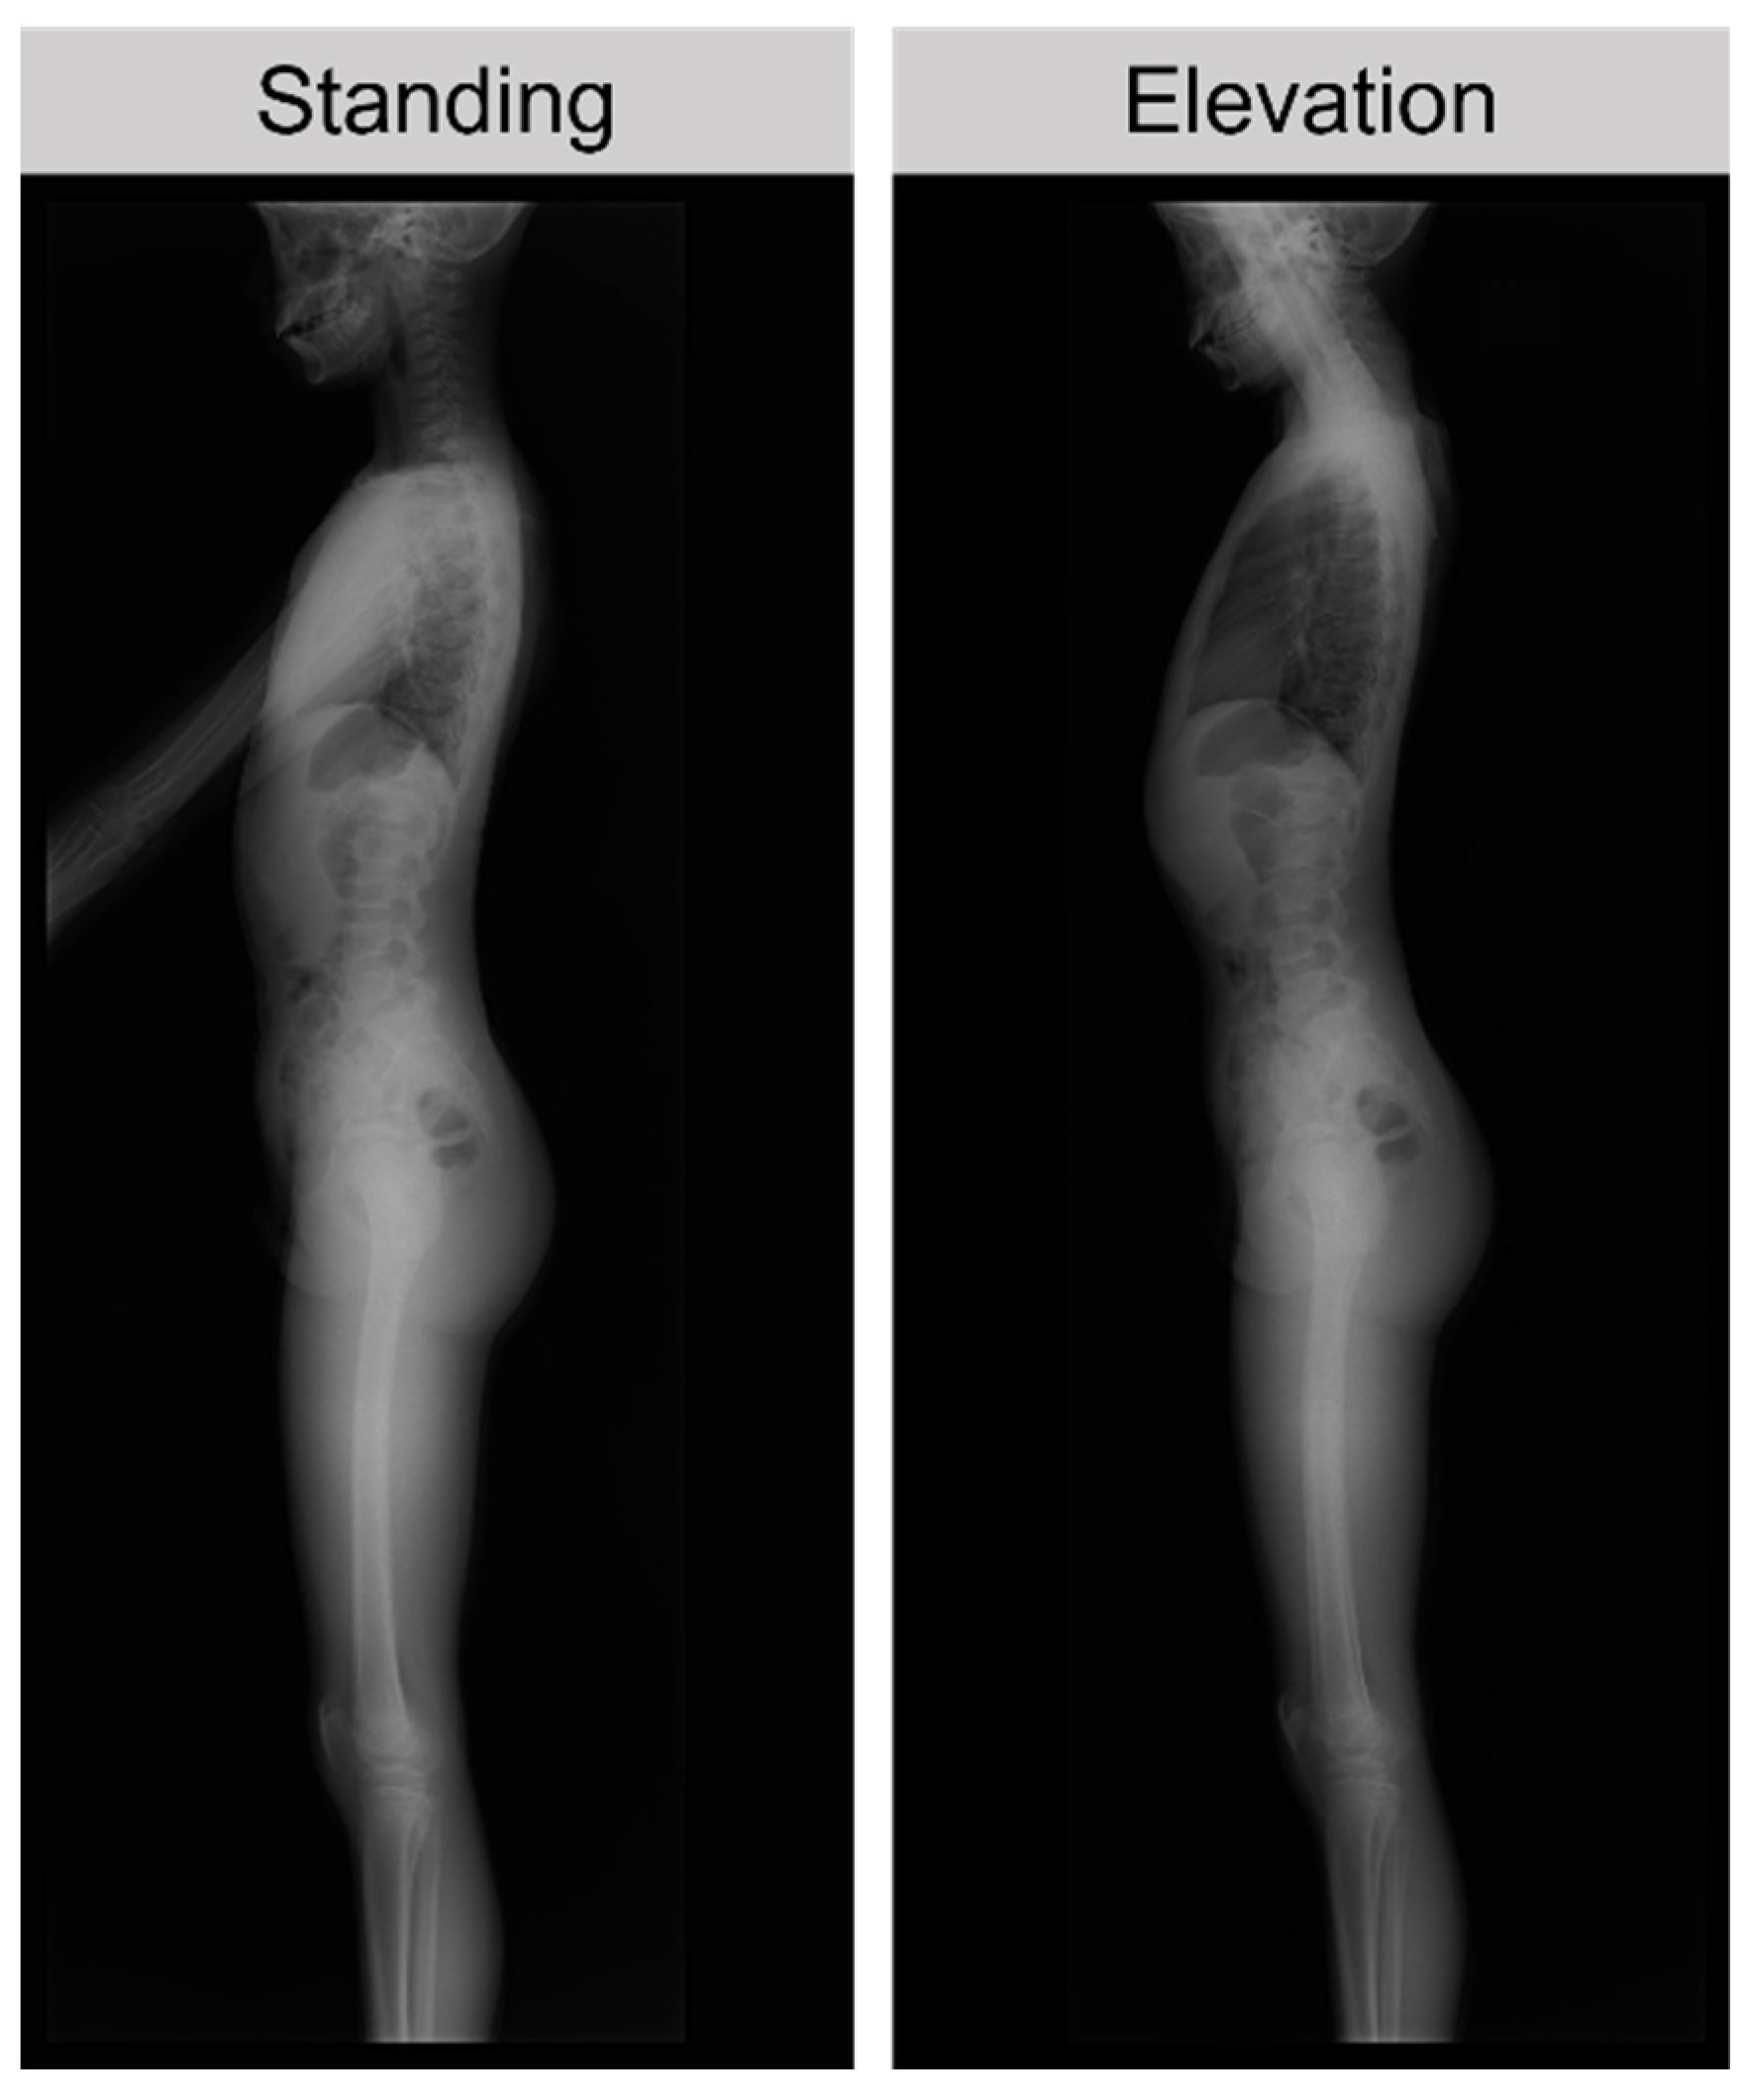

Spine Alignment in Standing and Maximal Upper Limb Elevation in Baseball Players with Lumbar Spondylolysis and Those without Low Back Pain

2.2. Measurements